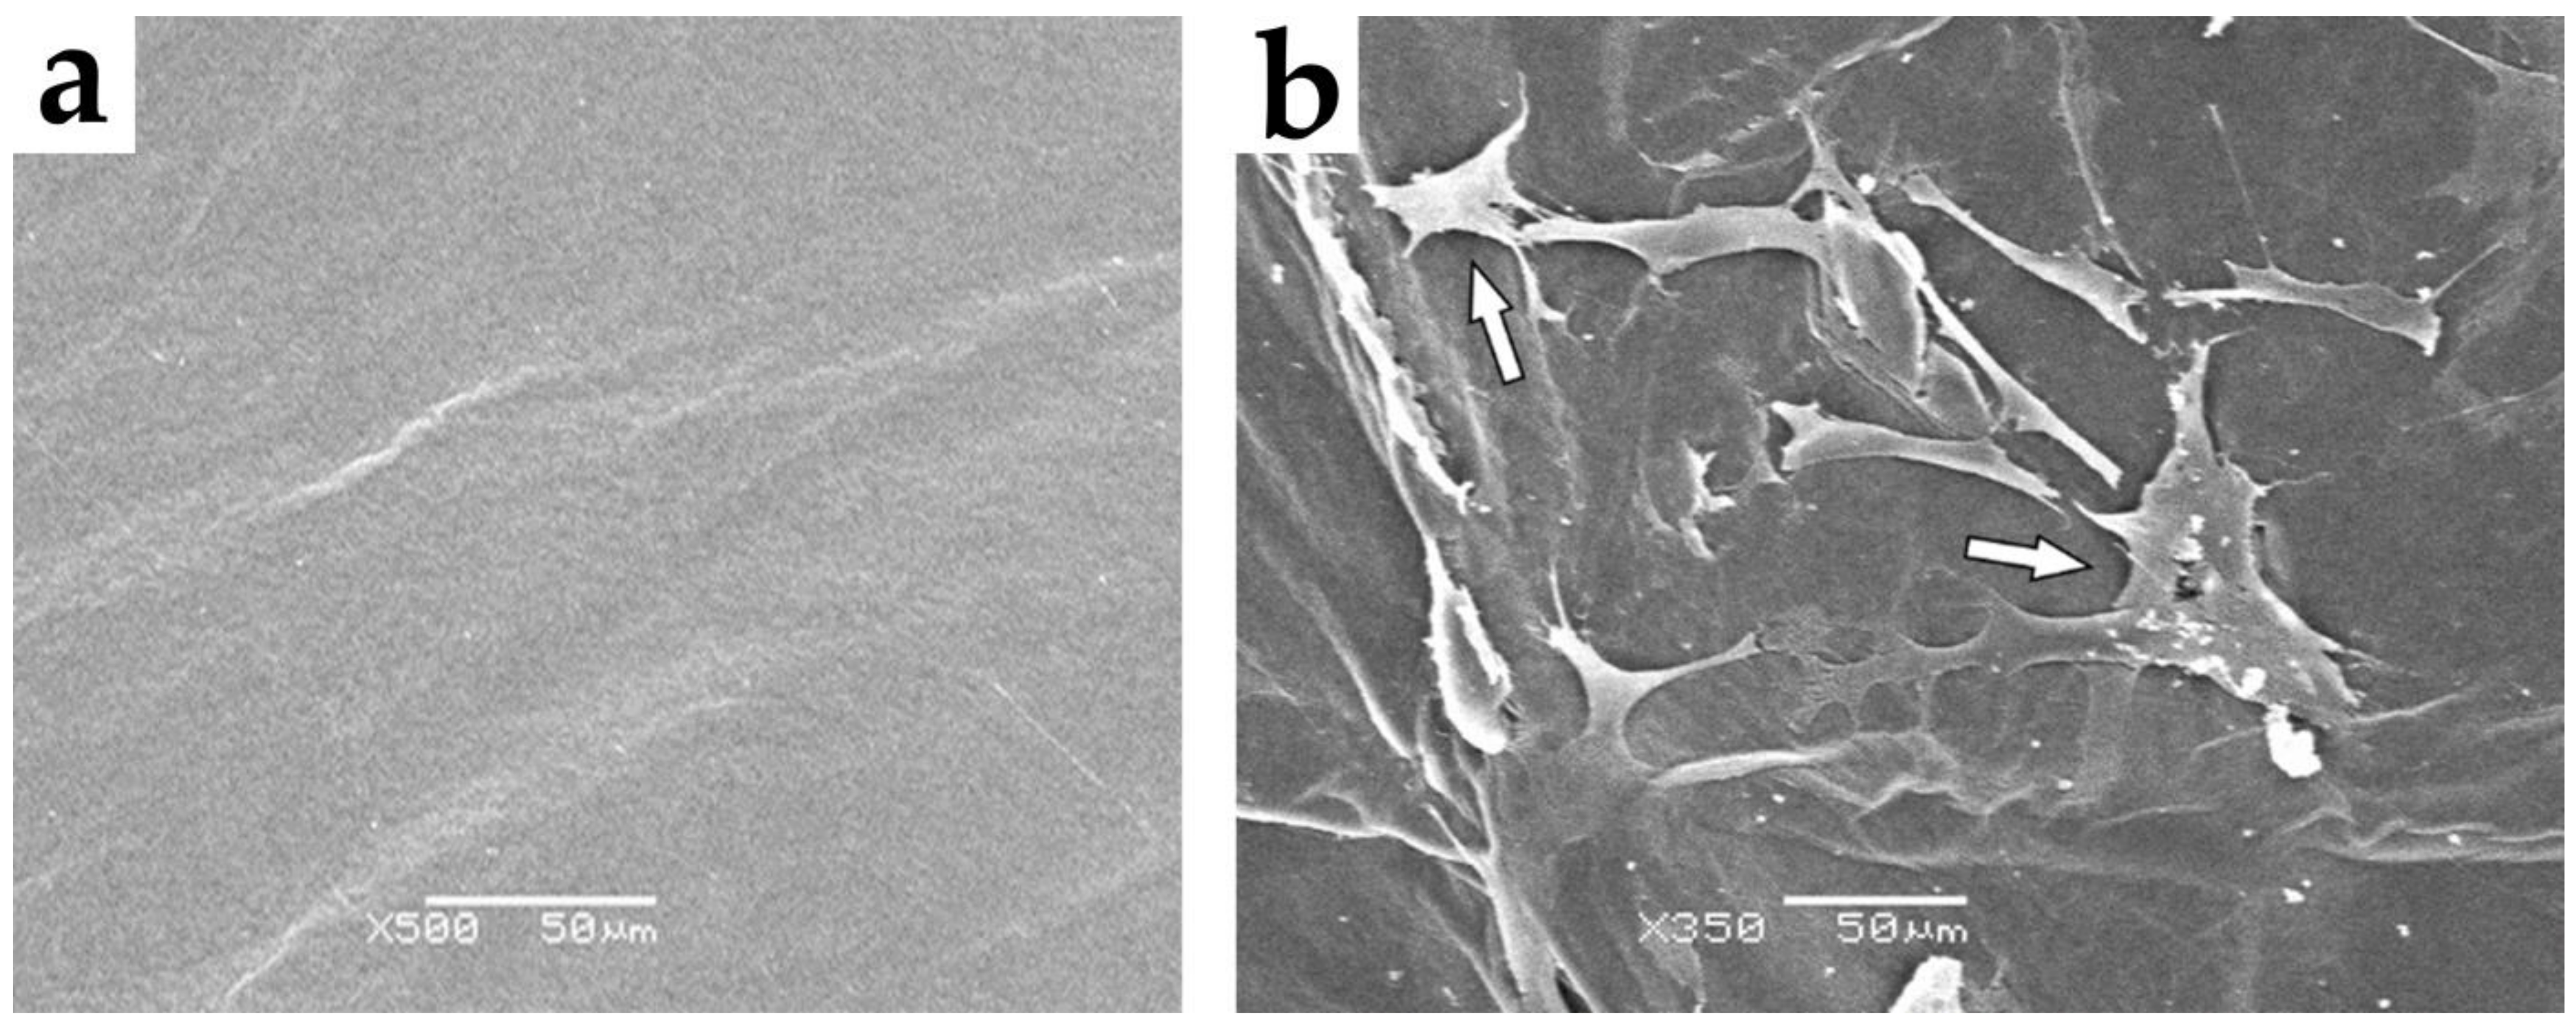

2.10. Scanning Electron Microscopy (SEM) Analysis

3.1. Cell Adhesion and Proliferation